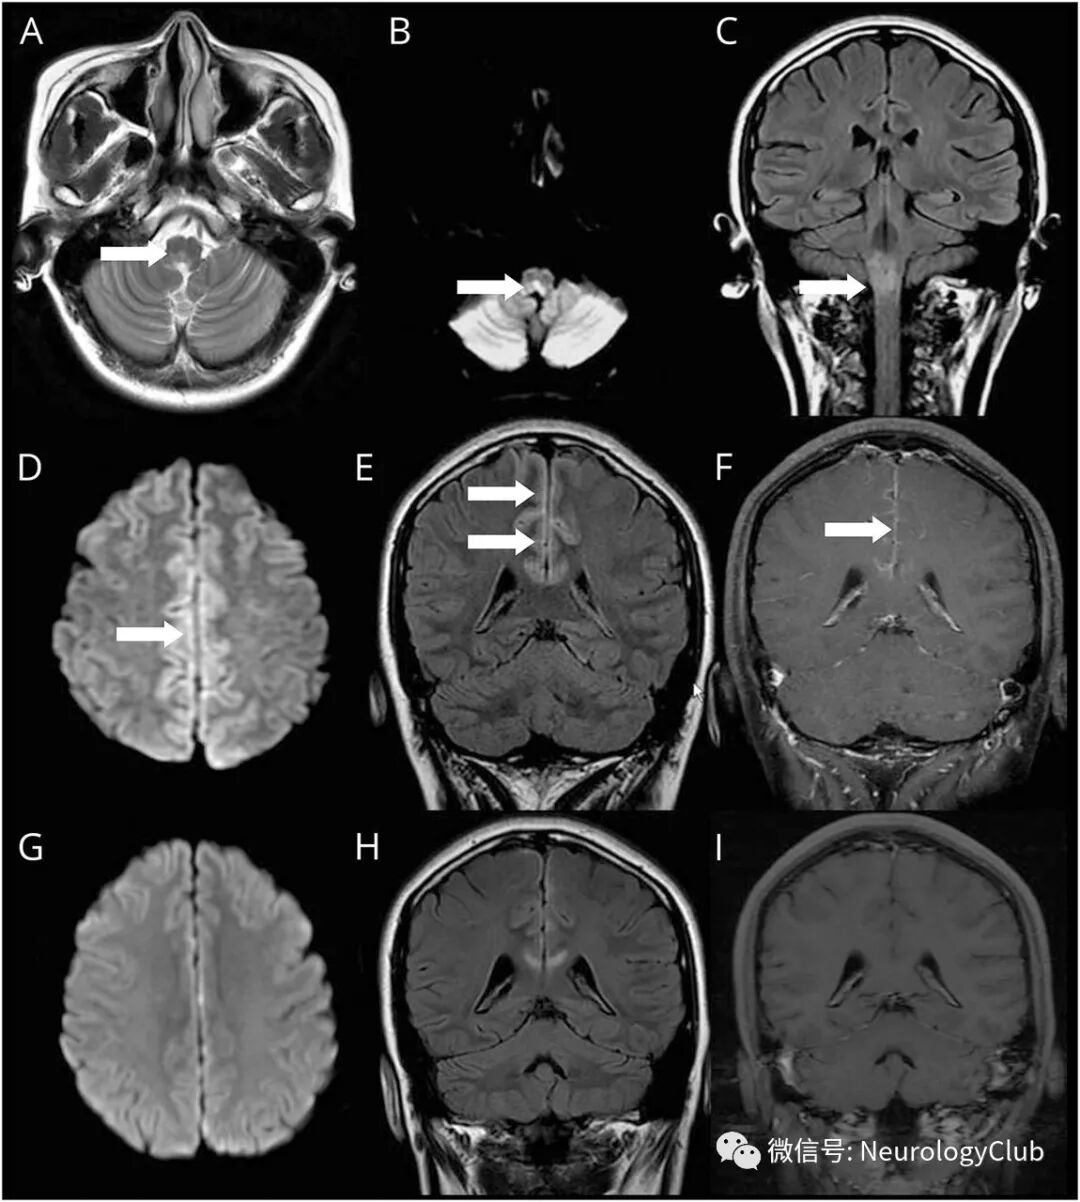

27岁女性,表现为头痛伴双下肢无力和麻木2周。两年前,患者有难治性呃逆和呕吐,MRI上可见极后区病变(图A-C)。最近的MRI可见邻近大脑镰的皮质损害伴柔脑膜强化(图D-F)。

(图:先前的T2WI,DWI和FLAIR图像[A-C]可见延髓高信号;最近的DWI和FLAIR可见局灶性皮质高信号[D-E]和柔脑膜强化[F];治疗后病灶改善[G-I])

感染性疾病筛查结果阴性。血清水通道蛋白-4-免疫球蛋白G阳性。免疫球蛋白和大剂量甲基强的松龙治疗后症状和影像学明显好转(图G-I)。